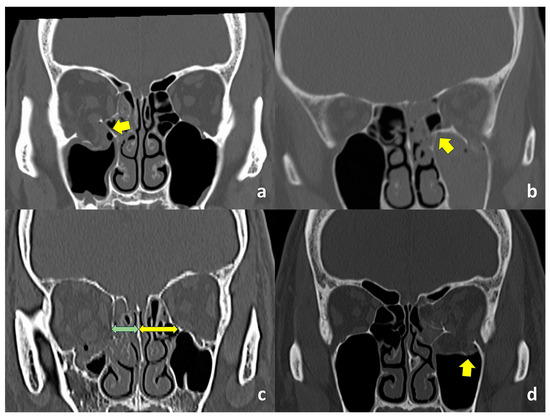

Axial and coronal CT images with bone and soft tissue window algorithms were obtained from all patients. Inferomedial strut fractures were diagnosed in cases with apparent strut fractures shown on coronal CT images (Figure 1a,b) or when the distance from the junction between the orbital floor and medial orbital wall and nasal septum was apparently shorter on the affected side (Figure 1c). Orbital fracture patterns, sites, entrapped orbital soft tissues in cases with trapdoor fractures, and concomitant nasal bone fractures were examined. Fracture patterns were classified into comminuted/open, hinged, trapdoor, and linear fractures [14]. The presence or absence of fractures of the orbital floor lateral to the infraorbital groove (Figure 1d) was checked [15]. Entrapped orbital soft tissues in cases with a trapdoor orbital fracture included the extraocular muscles and orbital fat.

Figure 1.

Computed tomographic (CT) findings. (a). The inferomedial orbital strut is not fractured (arrow). (b). The inferomedial orbital strut is fractured (arrow). (c). The distance from the junction between the orbital floor and medial orbital wall and nasal septum is shorter on the affected side (green arrow), compared to the unaffected side (yellow arrow). (d). The orbital floor lateral to the infraorbital groove (arrow) is fractured.

In the coronal view of orbital imaging, the inferomedial orbital strut can be identified as the bony junction between the medial and inferior orbital walls (Figure 1) [25]. The most common site of fracture, based on our previous study, was found to be the orbital floor medial to the infraorbital nerve [13]. This inferomedial portion of the bony orbit appears to be thinner than the portion of the orbital floor lateral to the infraorbital nerve [14], where the maxillary and zygomatic bones meet, and the integrity of the inferomedial strut becomes even more important to maintain support of the orbital contents. As a buttress of the orbit, the fracture of the inferomedial orbital strut, hence, can be confirmed on imaging when there is a shortening of the distance between this bony junction and the nasal septum (Figure 1c).